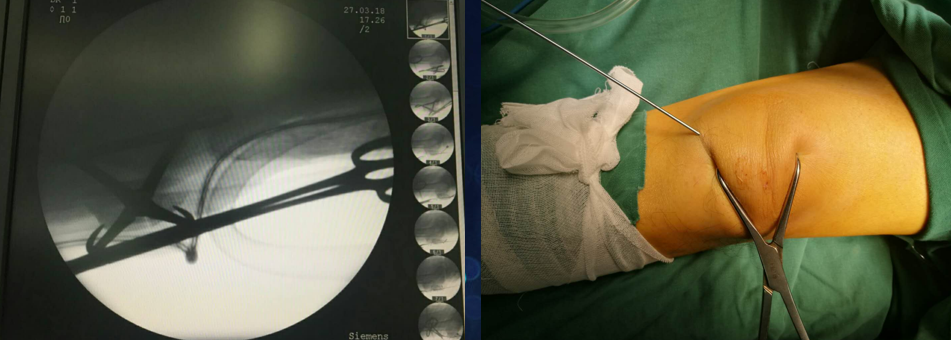

先扪及髌骨上下极及断端,用电钻于髌骨上极打一骨洞

利用腰穿针带过钢丝

再用利用腰穿针引导钢丝

收紧钢丝打结使其骨折端复位,透视发现复位欠佳

继续收紧钢丝,骨折复位,剪断钢丝

将钢丝埋于深处

由下方两钢丝口打入两髌骨

术后切口照片(无需缝合)

病房照(创口小,仅4个。最大的内下口约4MM)